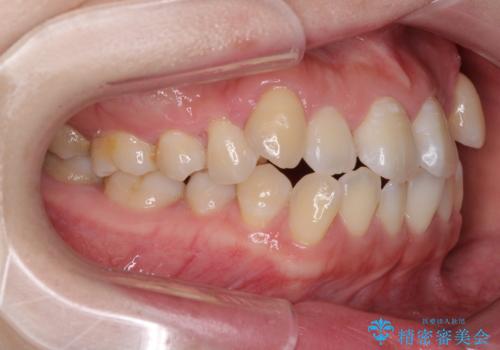

口元の突出感を改善 インビザラインによる非抜歯矯正

- 前歯がデコボコした上に口元が閉じにくいことを気にして来院された患者様です。

IPR(歯と歯の間を削る)と側方拡大では口の閉じにくさは改善できそうになく、一方で抜歯矯正を行うほどの突出感は認められませんでした。

親知らずを全て抜去し、歯列全体を後方に移動させることで口元の閉じにくさいを改善していくこととしました。

インビザラインでの歯列全体の後方移動は時間がかかりますが、しっかりと装着時間を守っていただいたので、スッキリとした口元に仕上げることができました。